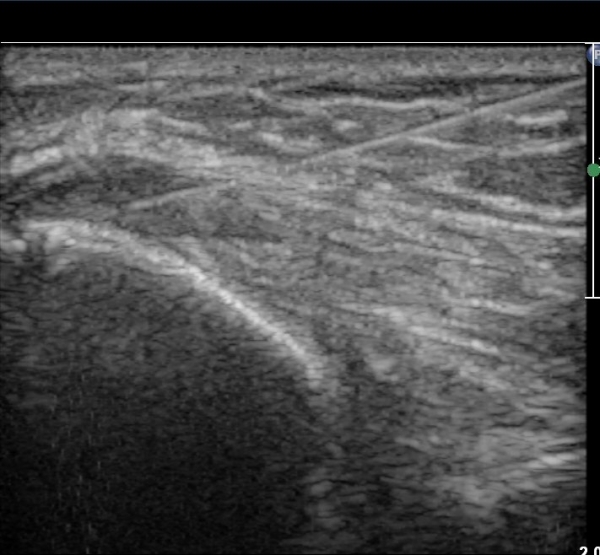

º´º¯ ºÎÀ§·Î ŽÃËÀÚ¸¦ À̵¿ÇÏ±â °Ç ºÎÂøºÎ Àú¿¡ÄÚ º¯¼ºÀÌ ¶Ñ·ÈÇÏ´Ù(±×¸² 5).

ÃÊÀ½ÆÄÀ¯µµÇÏ ÁÖ»çÄ¡·á »çÁøÀ¸·Î ¹Ù´ÃÀÌ º´º¯ ºÎÀ§¿¡ Á¤È®È÷ À§Çϰí ÀÖ´Â °ÍÀÌ º¸ÀδÙ(»çÁø 6).

Áֻ縦 ½ÃÇàÇÏ´Ï ÁÖ»ç¾×ÀÌ ¸¶Ä¡ ³¶Á¾¿¡ ÁÖ»çÇÏ´Â °Íó·³ ÁÖ»çµÇ¾î Àú¿¡ÄÚ º´º¯ ºÎÀ§°¡

ÆÄ¿­µÈ °ÍÀÓÀÌ È®ÀεȴÙ(÷ºÎ µ¿¿µ»ó).